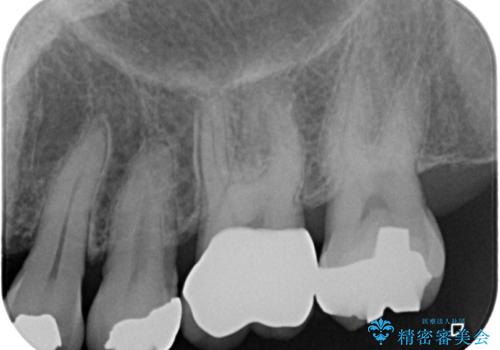

フロスの引っ掛かりもなくなり、食べ物もはさまりにくくなったそうで、満足されました。

定期的にメンテナンスで来院される患者様なのでレントゲン等で虫歯の進行を確認し、必要があれば隣在歯の治療に介入していく予定です。